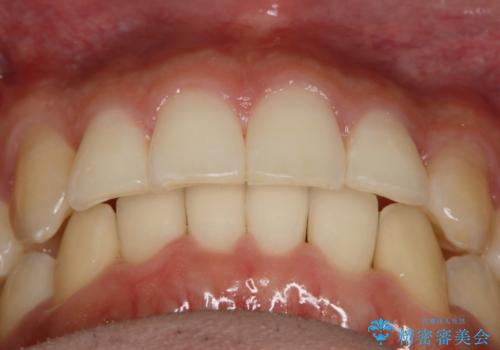

インビザラインで八重歯の治療

- 2年3ヶ月

マウスピースとマイクロインプラントを組み合わせることで、抜歯をしなくても歯並びを治すためのスペースを作ることができます。奥歯から順に移動させていくので前歯に変化が出るまでには時間がかかりますが、その分健康な歯を抜歯することなく理想的な歯並びを手に入れることができます。